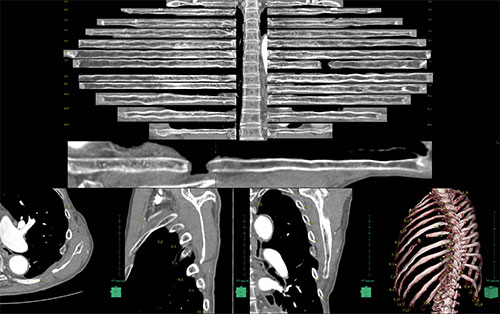

CTで撮影した画像を読み込むと肋骨、椎体の抽出、これらの骨番号の附番をおこないます。各々の領域を抽出することにより体幹の骨を一覧で観察することが可能です。

また、骨番号の附番により病変部の位置を同定しやすくなります。